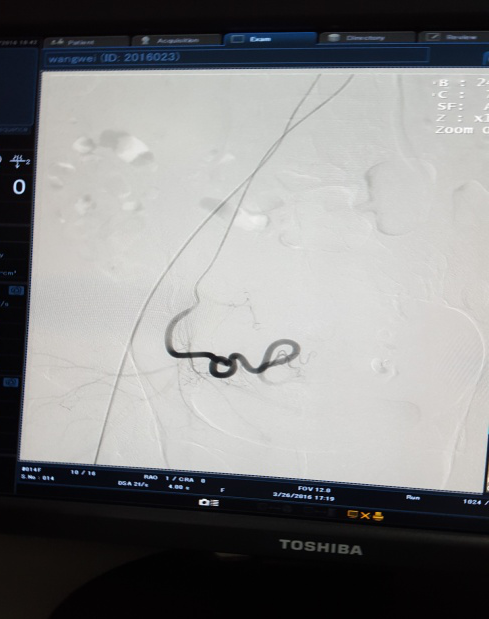

治疗前 左侧                              治疗后左侧分支血管消失

3月28日下午3点,在医院新导管室内,放射介入科主任张敏荣与任长德、李可峰医师成功地完成了新导管室建成后首例子宫腺肌症介入手术。该患者女性、40岁,因患子宫腺肌症,造成腹痛难耐,C臂下造影见:左子宫动脉增粗,分支数量增多、迂曲,用PVA颗粒栓塞迂曲的分支动脉,在妇产科保驾下,手术操作顺利。经过几天的对症治疗,各项检查指标符合出院标准,现病人已出院家中休养。该项手术的成功开展,又一次填补了市中医院该项之空白。